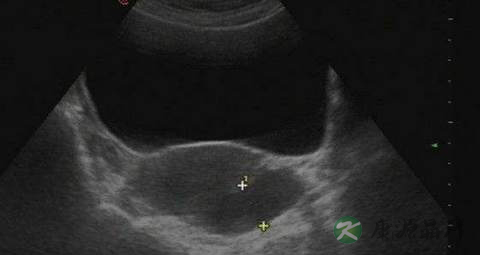

在临床上大多数妇女的盆腔积液是由于炎症引起,是盆腔存在炎性渗出物,如果不加以治疗的话,可以慢慢长大。病理性盆腔积液会导致月经紊乱、经血量多及痛经的出现,而且还会有腰骶部疼痛或下腹痛、白带增多、性感不快等症状。所以,病理性盆腔积液不仅影响月经,更会对女性朋友的日常生活带来诸多不便。